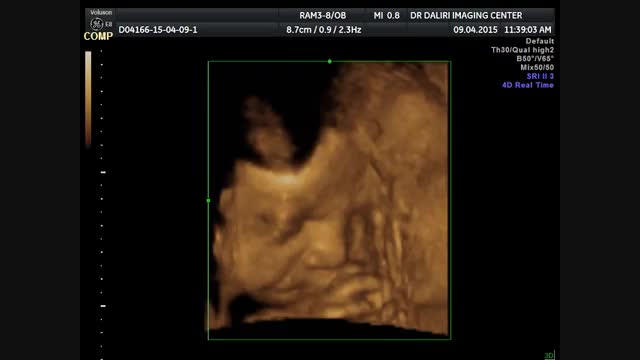

اسکن سه بعدی با استفاده از امواج فراصوتی و نرم افزار تصویری، تصاویر کاملا واضح و روشن از جنین ارائه می کند. اسکن ۳ بعدی تصاویری از نوزاد را در ۳ بعد نشان می دهد. بدون شک این حالت بسیار هیجان انگیز است چون اغلب مادرانی که سونوگرافی دو بعدی انجام می دهند از دیدن تصویر سیاه و سفید و تا حدودی تار ناامید می شوند. با اسکن ۳ بعدی شما پوست جنین را می بینید نه اندام داخلی اش را. حتی شما می توانید شکل دهان و بینی او را ببینید.